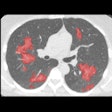

Thirona unveils AI software for COVID-19 analysis

Behold.ai receives CE Mark for chest x-ray AI software

Behold.ai joins forces with Wellbeing on AI for COVID-19

Behold.ai trains AI to detect COVID-19 on x-ray